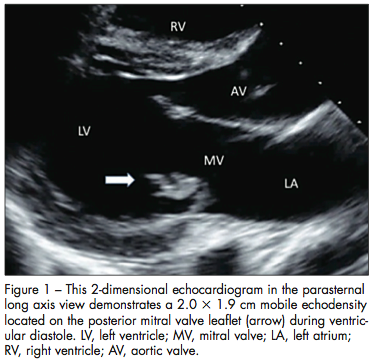

Echocardiographic images are obtained (Figures 1, 2, and 3). They demonstrate severe mitral regurgitation with a mobile, echogenic density on the posterior leaflet of the mitral valve (2.0 by 3 1.9 cm).